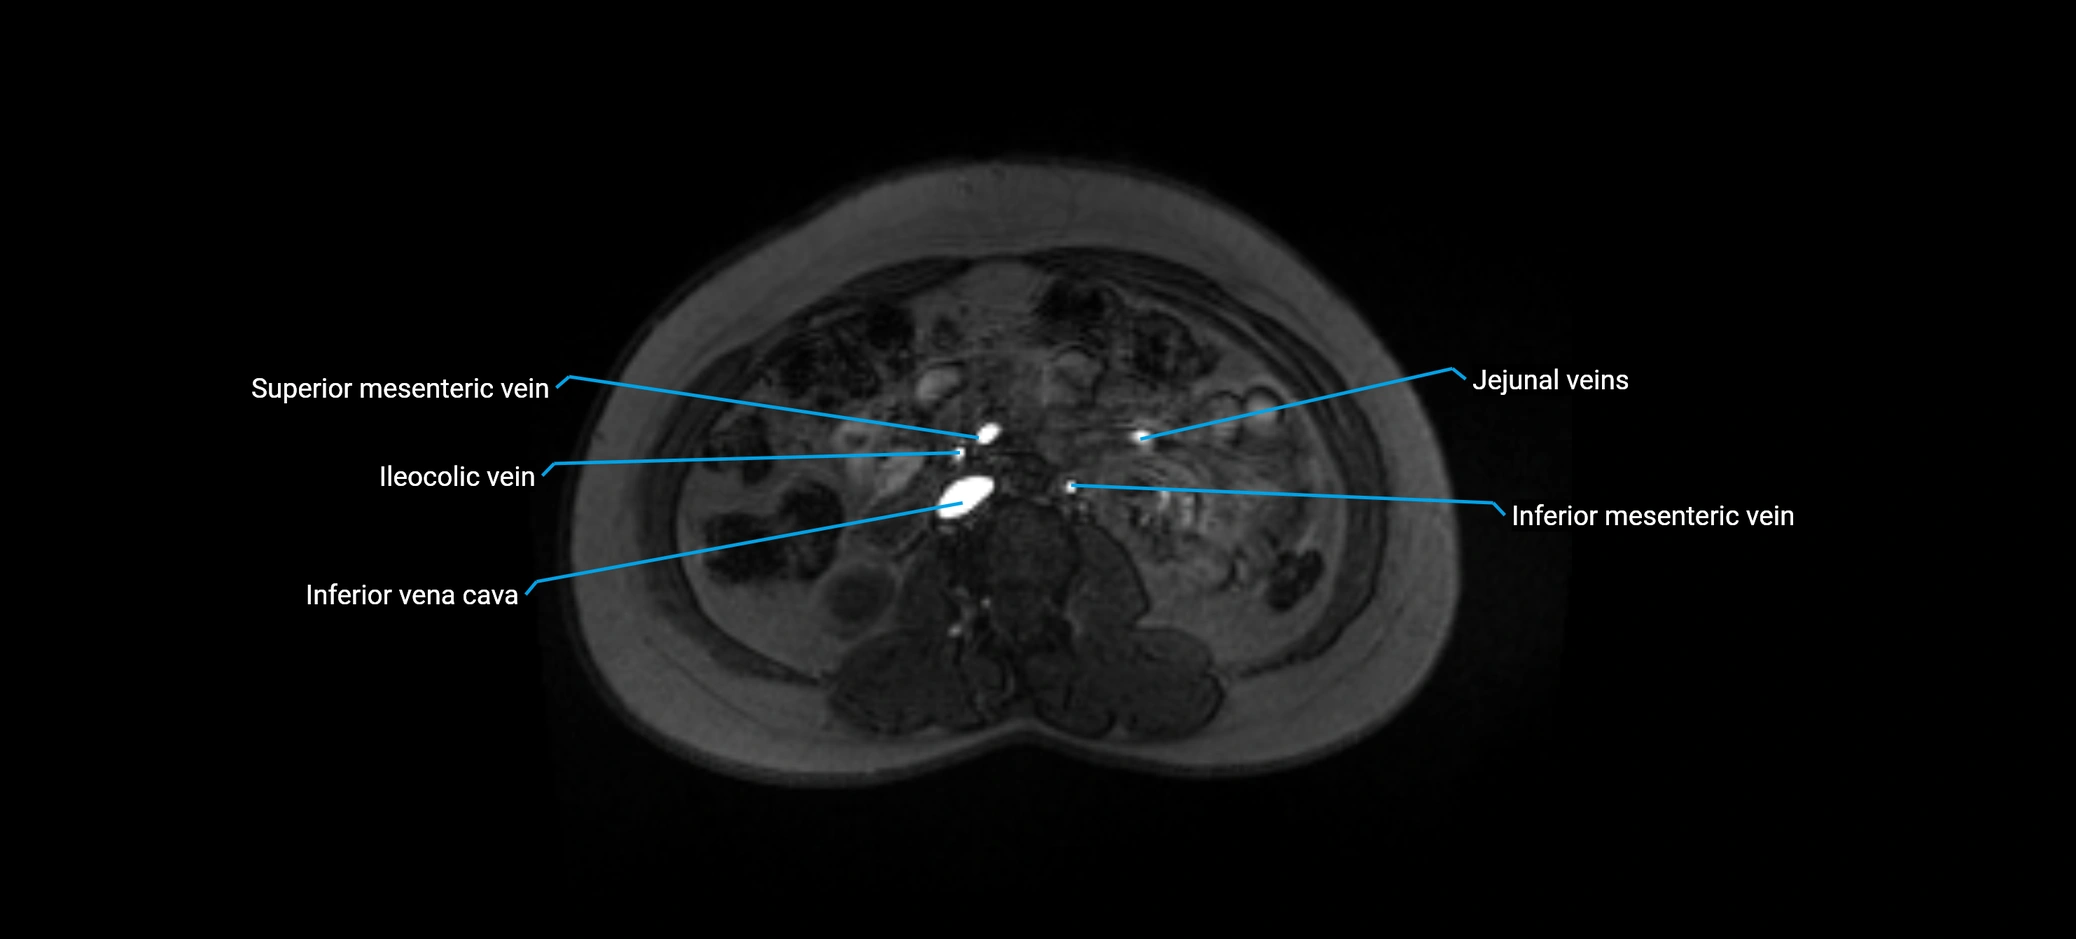

MRI image

image